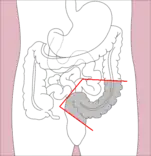

- Right hemicolectomy and left hemicolectomy refer to the resection of the ascending colon (right) and the descending colon (left), respectively. When part of the transverse colon is also resected, it may be referred to as an extended hemicolectomy.[5]

Right hemicolectomy

Right hemicolectomy Right extended hemicolectomy

Right extended hemicolectomy Left hemicolectomy

Left hemicolectomy Extended left hemicolectomy

Extended left hemicolectomy - Transverse colectomy is also possible, though uncommon.